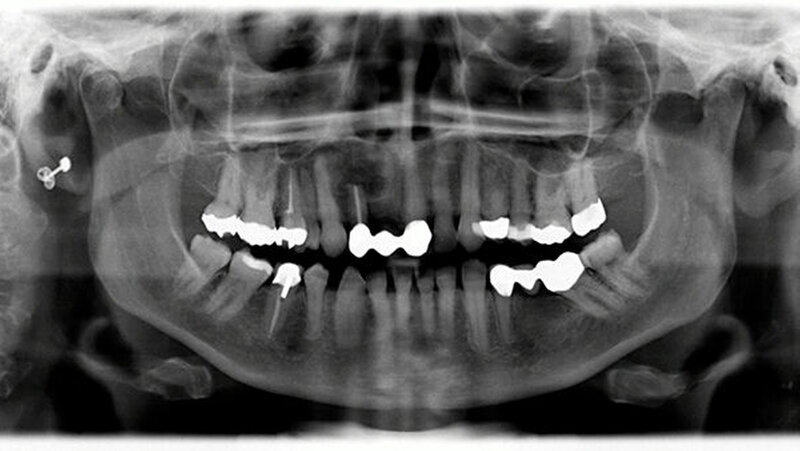

Zudem wurde eine postoperative Röntgenkontrolle mittels OPG durchgeführt (Abbildung 7). Bei optimaler Mundhygiene war der Heilungsverlauf stadiengerecht, ohne dass Dehiszensen oder eine Infektion aufgetreten wären.